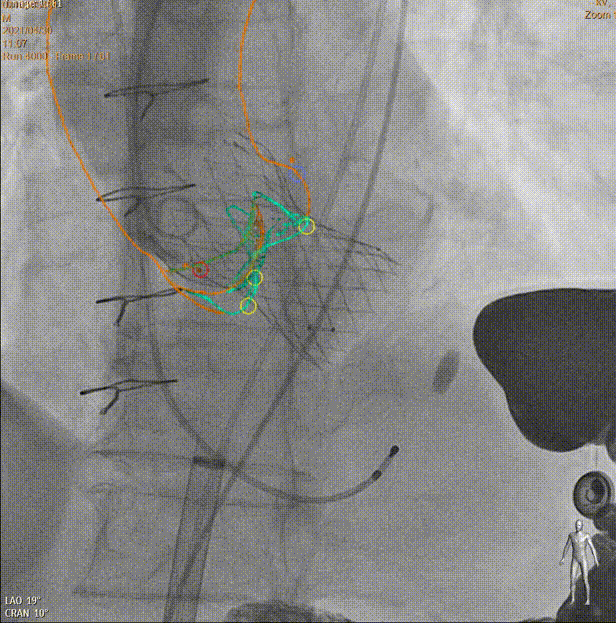

Heart Navigator通过将CT或MRI数据与实时X光透视影像融合,动态呈现手术器械与解剖结构的关系。医生在术中能够实时看到关键部位的分布和标记点,确保手术路径的安全性和准确性。这种实时导航技术还支持术中影像的自由调整,使医生可以快速响应突发情况。

TAVI:主动脉瓣与实时透视融合

LAAO:左心耳与透视实时融合